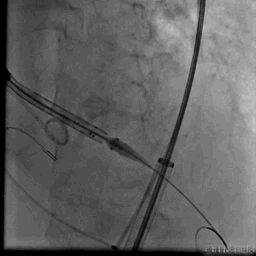

VenusA26定位

瓣膜完全释放